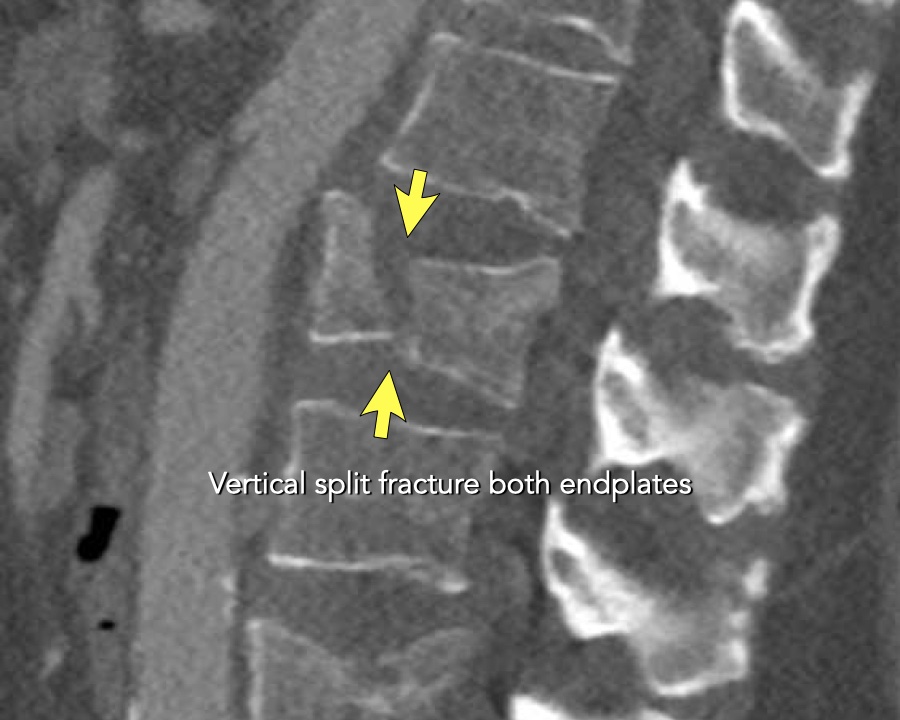

A2 Split fracture

A2 is a fracture of both endplates without involvement of the posterior wall of the vertebral body.

What is the highest AO-type of injury?

Findings:

- No C or B injury

- Fracture of the vertebral body with involvement of both endplates (1+1 points), no posterior wall involvement

Conclusion

injury type A2